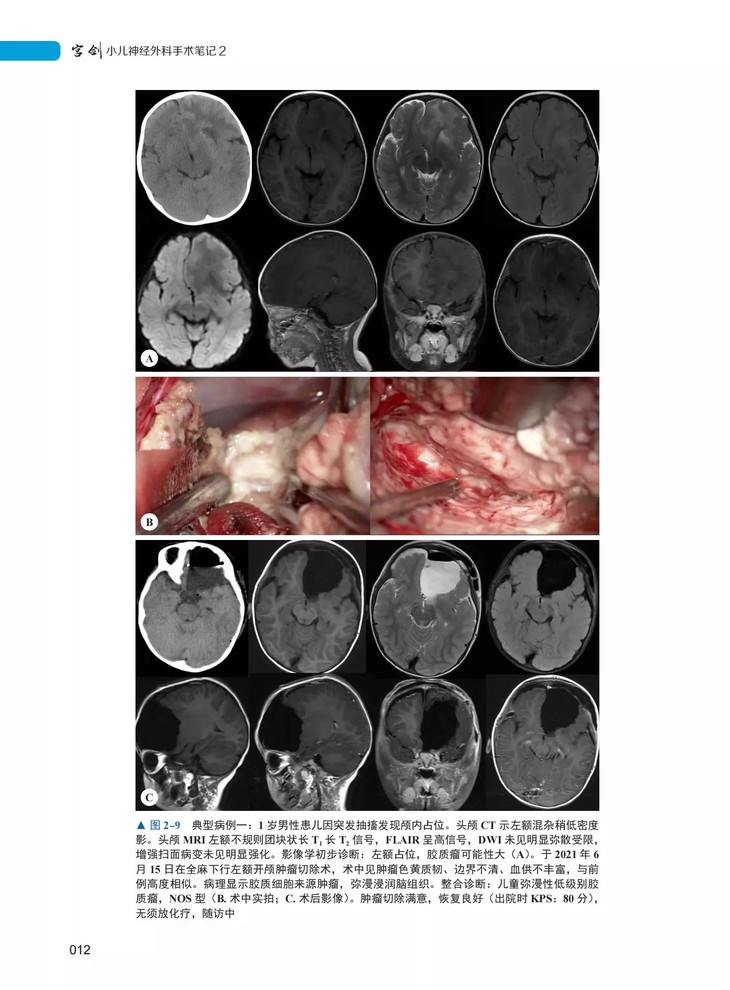

本书由北京天坛医院小儿神经外科主任宫剑教授主编,是继《宫剑小儿神经外科手术笔记 1》之后,宫剑教授及其团队“十年十部手术笔记”出版计划中的第 2 部。宫剑教授专注于儿童颅内肿瘤及各类先天性疾病外科治疗近 20 年,带领团队每年完成手术千余例,数量及质量均达到国际先进水平。本书上篇为每年千余例临床病例中精心挑选的 50例典型病例,详细介绍患儿的主诉、临床症状和体征、术前术后影像学特点、手术操作要点、术后病理及蛋白基因检测结果、术后转归等,结合国内外最新研究进展,总结出该病种的治疗经验与手术体会。下篇则汇总了宫剑教授及马振宇主任接受神外新媒体的最新访谈,就部分病例的天坛诊疗规范进行了详细解读,对小儿神外的历史进行了系统回顾。本书是第一手临床资料总结,实用性强,适合作为日常临床诊疗工作的参考资料,也适于广大患儿家长参考阅读。